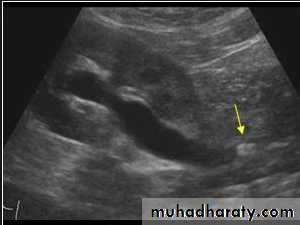

1-Dilatation of the P.C.S. appears as multilocular fluid collection within central echo complex.-With more severe distention, dilated calyces appear as Multiple cysts but communicating with each other unlike true cysts.

2-Stones larger than 5 mm are easily seen on US but smaller ones may be missed.

-They produce intense echoes (hyperechoic) and cast acoustic shadows.

-Proximal and distal ureteric dilatation can be easily identified unlike mid-ureteric dilatation, and stones located in the middle third of the ureter are hard to be demonstrated unlike upper and lower ureteric stones (especially those lodged in the vesico-ureteric junction or pelvi -ureteric junction) which are easily identified by ultrasound.